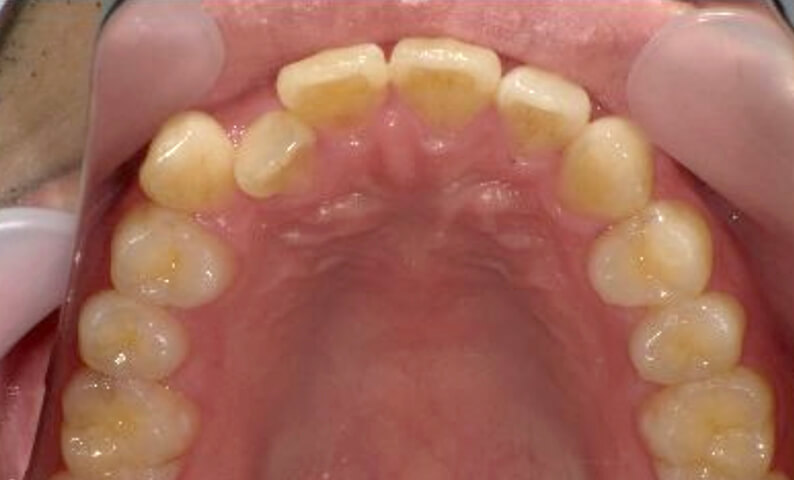

症例_024 上顎だけの部分矯正

治療期間:7ヶ月金額:30万円+税女性前歯のガタガタ上の前歯だけ

| Before | After |